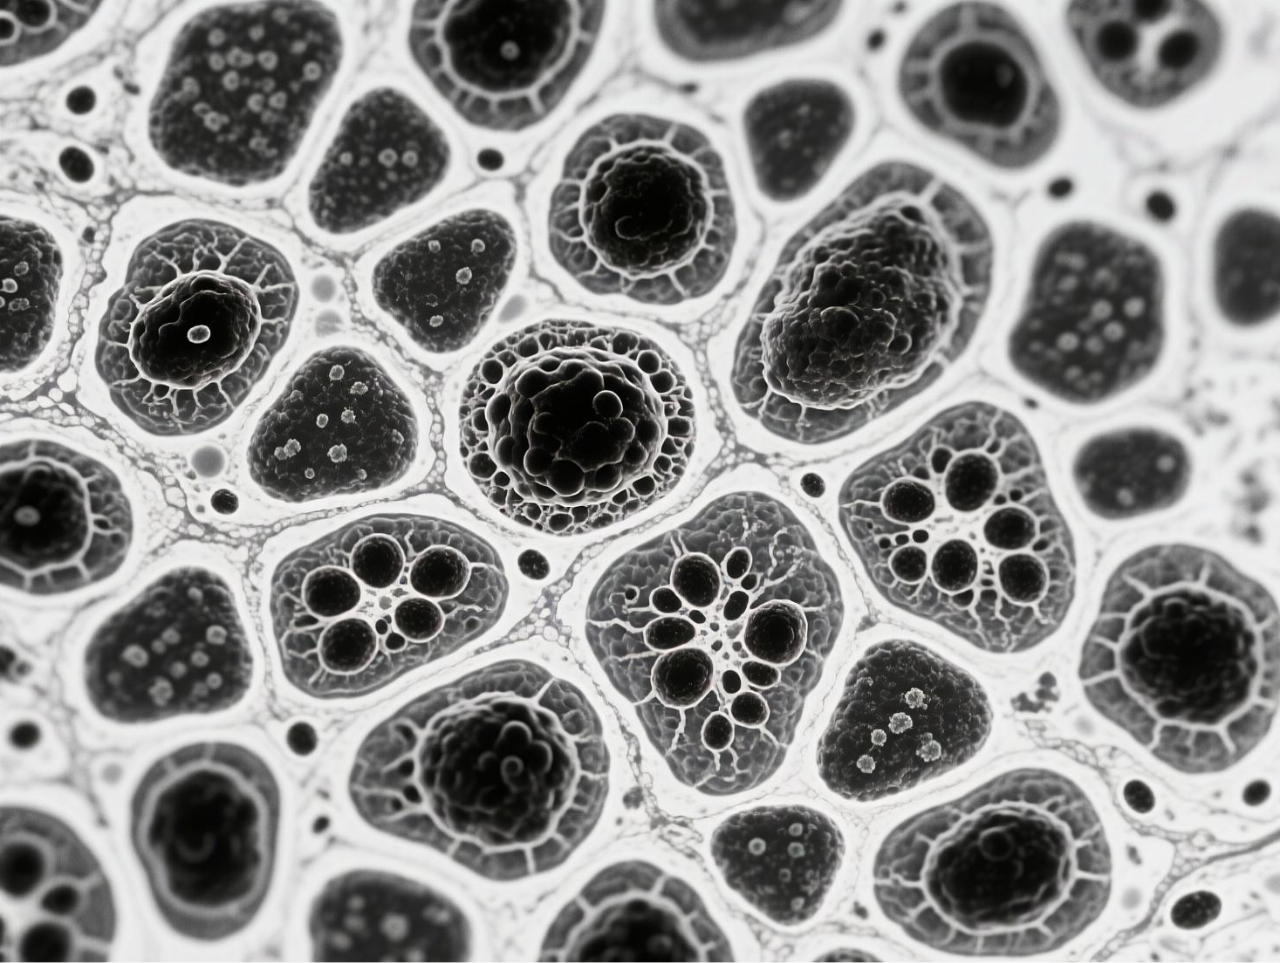

臺式掃描電鏡在本研究中發揮了關鍵的表征作用,為微氣泡系統的結構驗證提供了直觀而精確的證據。研究團隊使用澤攸科技ZEM18臺式掃描電鏡對凍干后的BCG-MBs進行金濺射鍍膜處理后,在不同放大倍數下觀察其表面形態,清晰地展示了微氣泡規則的球形結構以及BCG在微氣泡表面的不規則分布狀態。這一表征不僅確認了微氣泡制備工藝的成功,還直觀揭示了BCG在微氣泡中的物理分布特征,為理解藥物釋放機制提供了結構基礎。掃描電鏡圖像作為重要的形態學證據,有力支持了后續對微氣泡浮力特性、藥物釋放行為及生物效應的分析,是連接材料設計與功能驗證的關鍵環節。

圖 BCG-MBs的制備與表征